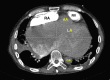

An Audaciously Aneurysmal Atrium

Keywords: Echocardiography; Imaging; Mitral stenosis; Rheumatic heart disease.